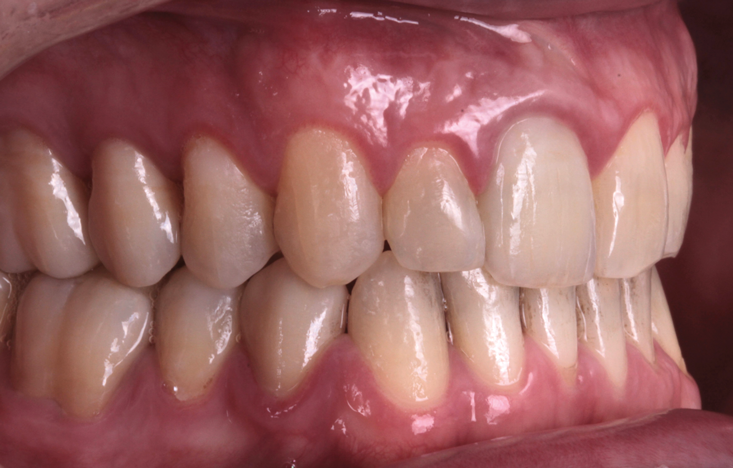

Fig 8. A class III adult male patient required surgical orthodontic treatment. The patient had anterior and posterior crossbites and required leveling of a deep curve of Spee during presurgical orthodontics.

Figure 8

Fig 9. A class III adult male patient required surgical orthodontic treatment. The patient had anterior and posterior crossbites and required leveling of a deep curve of Spee during presurgical orthodontics.

Figure 9

Fig 10. A class III adult male patient required surgical orthodontic treatment. The patient had anterior and posterior crossbites and required leveling of a deep curve of Spee during presurgical orthodontics.

Figure 10